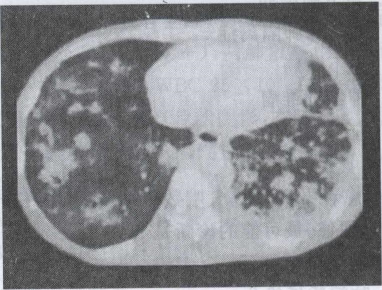

26.患者男,27岁,干咳,呼吸困难半月余,有艾滋病病史半年余,结合CT检查,最可能的诊断是()